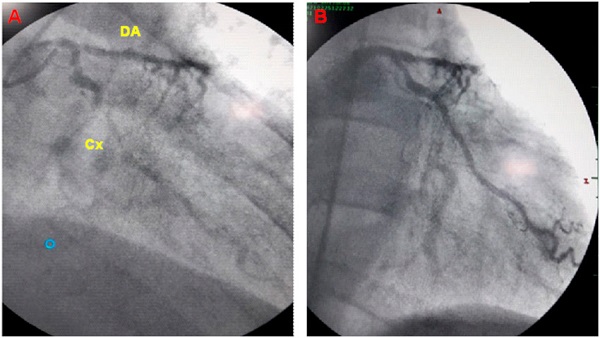

Debido a las características ambulatorias de nuestro centro, se decidió derivar al paciente a un centro de alta complejidad, donde se internó en Unidad Coronaria y se realizó cinecoronariografía, que evidenció oclusión de la arteria Descendente Anterior (Figura 2), con circulación colateral desde la Coronaria Derecha y estenosis significativa en la arteria Circunfleja. El paciente fue sometido a angioplastia coronaria, con colocación de 2 stents. Egresó de la sala de Hemodinamia estable, sin complicaciones, y recibió el alta médica pocos días después. Cabe acotar que, debido a los antecedentes de arritmia maligna, su equipo médico decidió la colocación de un cardiodefibrilador automático implantable.